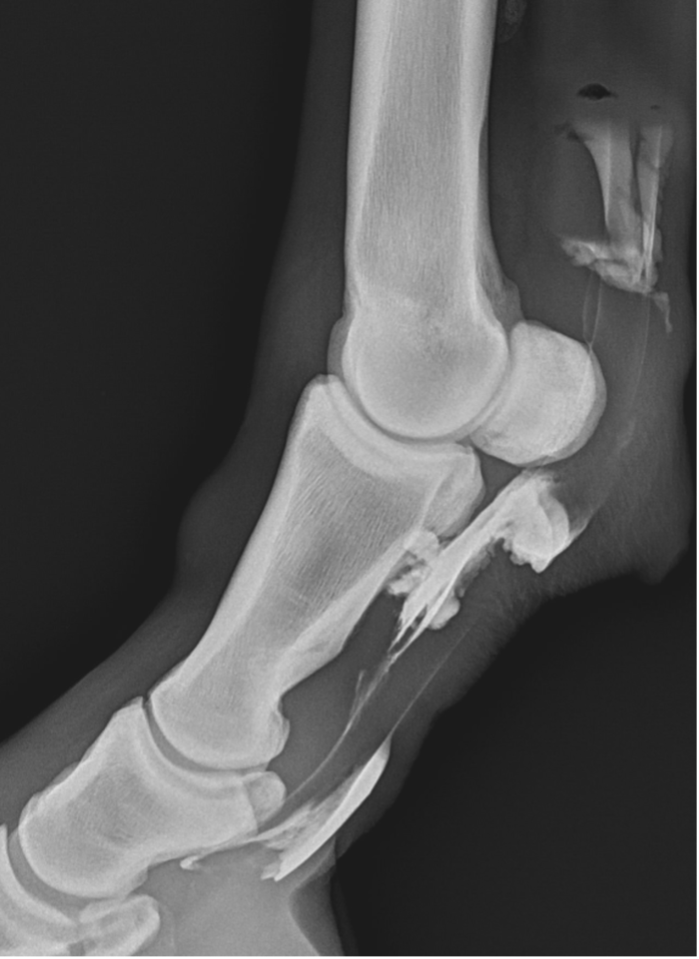

Upon further examination, contrast radiographs and ultrasound scans failed to identify any significant abnormalities apart from swollen synovium within the DFTS. To address this issue, our veterinary team administered 5mg of triamcinolone acetonide along with 20mg of HA, complemented by a compression wrap. Subsequently, the horse underwent a two-week confinement period in a small yard, followed by gradual reintroduction to exercise through 10 minutes of hand walking twice daily, with the distal limb wrapped for additional support.

However, when the condition resurfaced, our client chose to pursue tenoscopy, which fortunately revealed no clinically significant abnormalities. Following the procedure (2-weeks post-surgery), 2ml (50mg) of Arthramid was injected into the sheath, followed by two weeks of hand walking and a seamless transition back to regular riding activities.